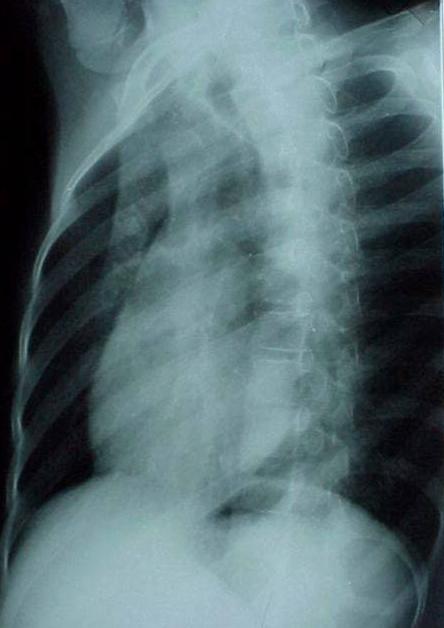

照片名称:胸腔积液

照片名称:左侧胸腔积液

照片名称:大量胸腔积液

照片名称:卧位胸腔积液

照片名称:右侧胸腔积液